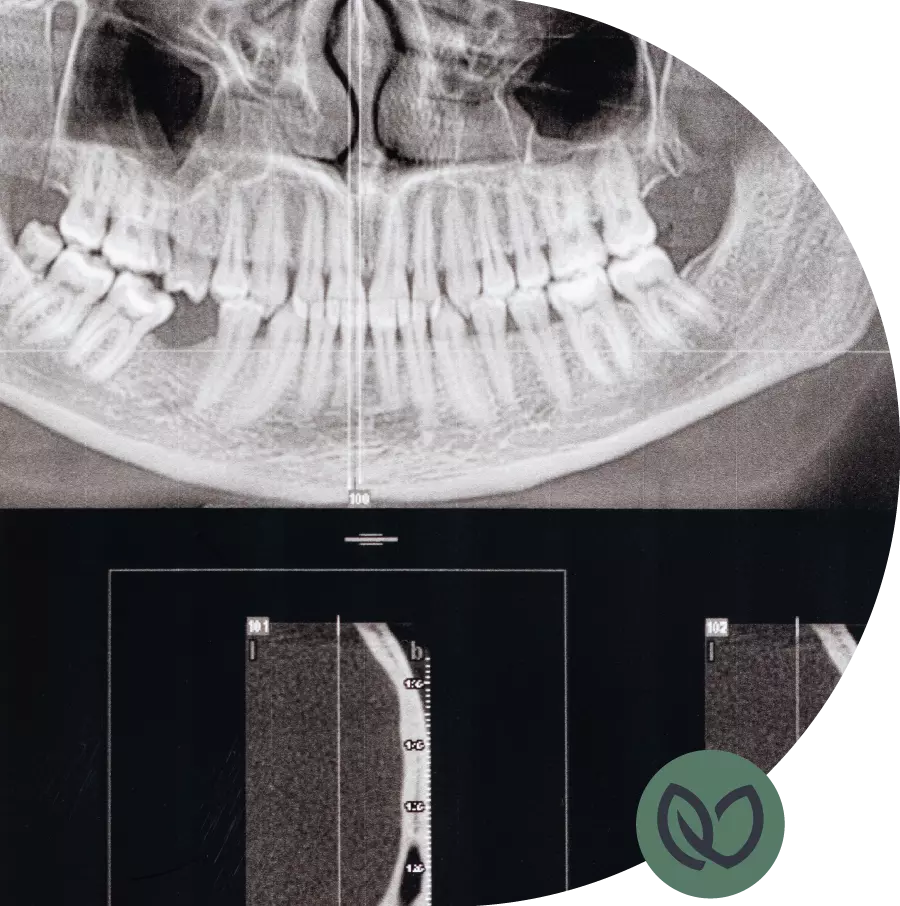

Before proceeding with the extraction, the dentist will take the necessary X-rays and evaluate your medical history. This helps determine the best approach and minimize potential complications. The dentist will administer local anesthesia to numb the area and reduce any discomfort.